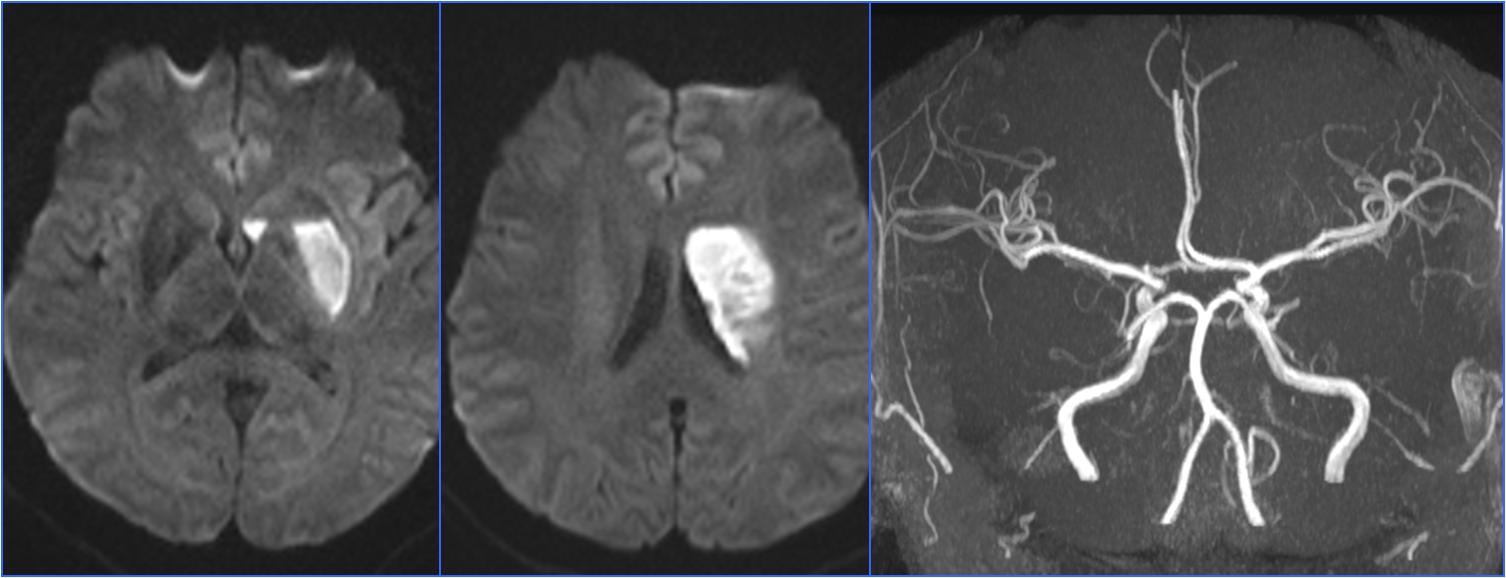

Case9 房间隔缺损脑栓塞

》女,29岁,既往健康

》8:10突发言语不清、右侧肢体无力

》9:05分到达急诊科,NIHSS 10分

》9:26完成头MRA检查

》10:35行股动脉穿刺

》10:58血流重建 11天后出院,NIHSS 0分

▼术前头MRA

▼术后24小时CT

》查找病因

》TCD发泡试验提示右向左固有型大分流

》经食道超声提示房间隔缺损大小约8mm

》转心外科行微创房间隔缺损封堵术